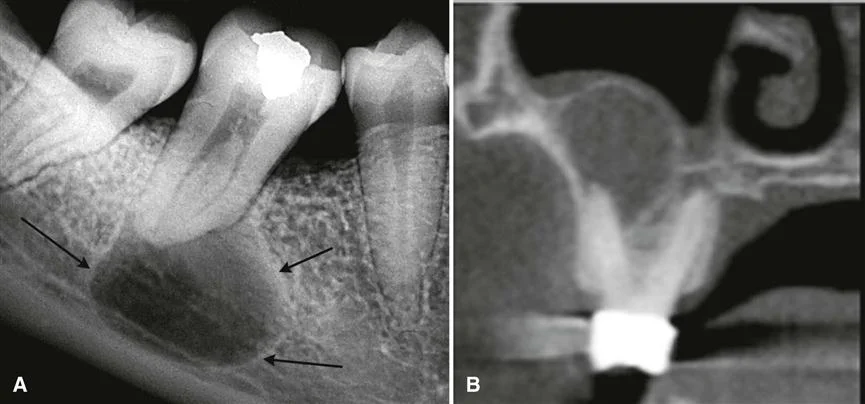

Рентген

Образование не имеет четких контуров.

Заметна капсула круглой формы. Границы четкие.

рентген кисты зуба фото